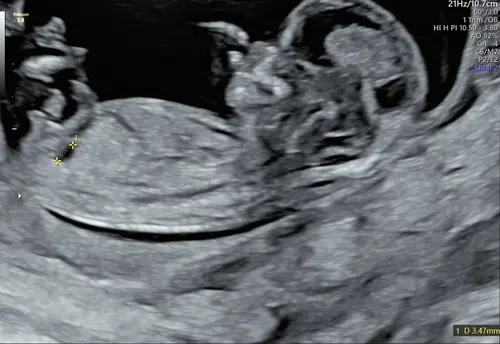

Echo van 12+6 maar ik geloof dat onze eigenwijze draaikont de beentjes in de weg legt 😅😅 de hele echo was uberhaupt 1 grote uitdaging dus de andere foto's zijn niet beter

Sorry geen nub te zien